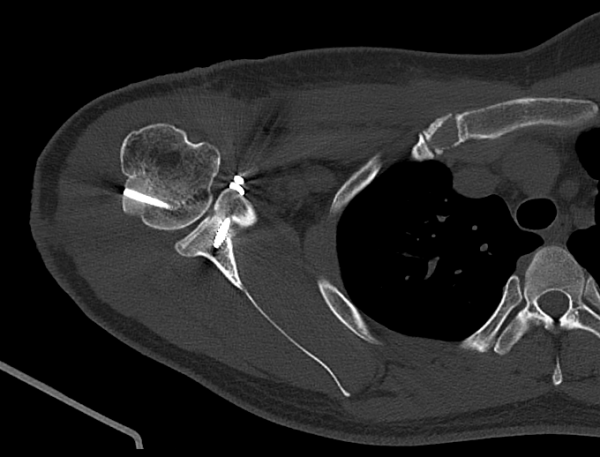

① 상완골두 동종골 이식 (Humeral Head Reconstruction)

결손 부위에 맞게 이식골을 정교하게 다듬어

정상 관절면과 일치하도록 맞추는 과정이 매우 중요했습니다.

여기서 조금이라도 오차가 발생하면 향후 관절 운동 범위에 제한이 생길 수 있습니다.

Headless Screw 2개로 고정

안정적이고 생역학적으로 유리한 고정을 위해 headless screw를 사용했습니다.

Open Latarjet 시행

부리돌기를 조심스럽게 떼 내어 관절와 결손부위에 이식하여 관절 전방의 구조적 안정성을 확보했습니다.

이 술기가 병합되어야만 재탈구 위험을 실제로 줄일 수 있었습니다.

수술 후 첫 CT 결과에서 이식된 상완골두는 정렬 상태가 매우 우수하고, 결손 부위를 정확하게 메우고 있었습니다.